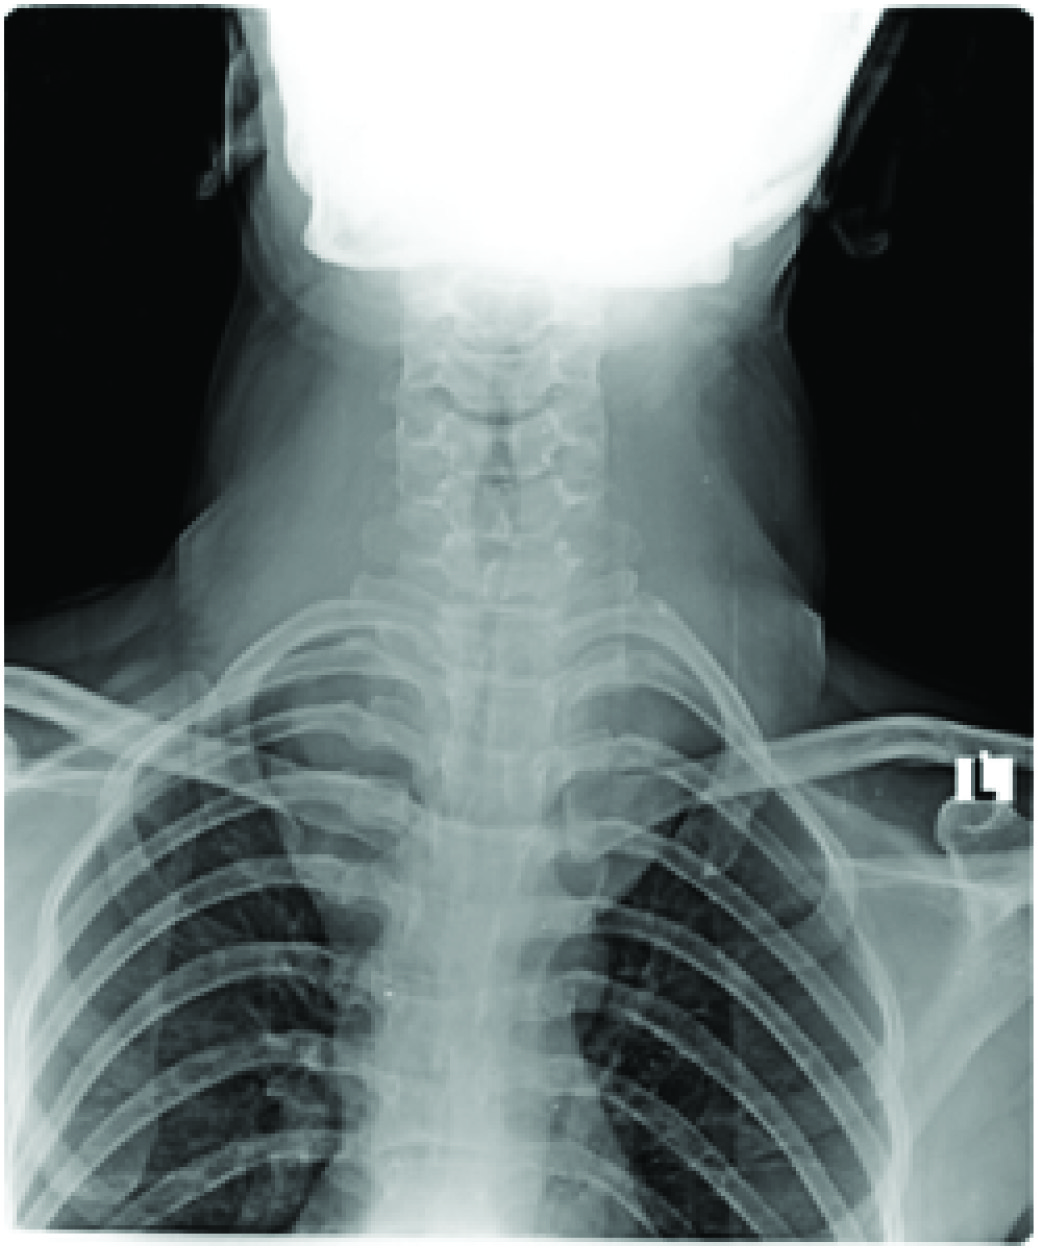

A 42-year-old lady weighing 42kg presented with large goiter since 10y. She denied history of change in voice and difficulty in breathing. She had no other comorbidities and was not on any medications. On examination her vitals were normal. A neck swelling was 15 × 10 cm in size, occupying entire anterior aspect of neck and the lower border of swelling was not palpable [Table/Fig-1]. Airway examination revealed mouth opening less than two fingers and Mallampati score 3. Neck extension was limited and flexion was severely restricted. Electrocardiogram and 2D echocardiogram were normal. Her thyroid profile and routine investigations were normal. Indirect laryngoscopy showed bilateral mobile vocal cords and posteriorly pushed trachea. X-ray neck revealed a large thyroid mass extending retrosternally with significant tracheal narrowing [Table/Fig-2]. CT scan showed diffusely enlarged thyroid gland extending from angle of mandible to retrosternal space upto arch of aorta, significantly compressing trachea with narrowest luminal diameter of 3.5 mm [Table/Fig-3].

X-ray showing tracheal compression